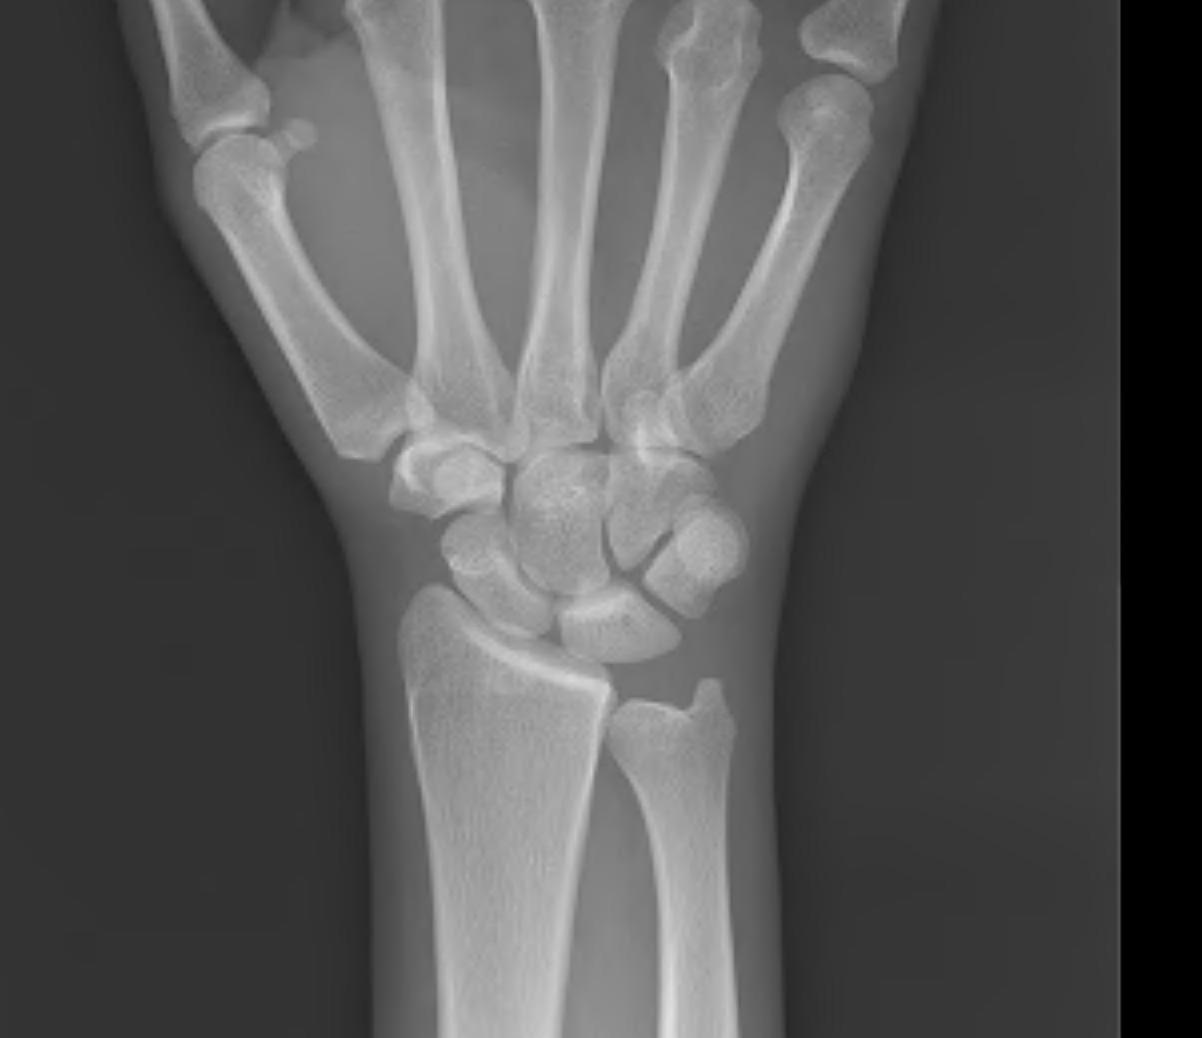

Ulna Variance

Supination and pronation alter variance

90 / 90 view (elbow 90° / shoulder abducted 90°)

- neutral supination / pronation

- PA film with wrist in neutral

- line from lunate fossa and ulna head

ulnaulna

Ulna neutral

Ulna positive

ulna negulna

Ulna negative